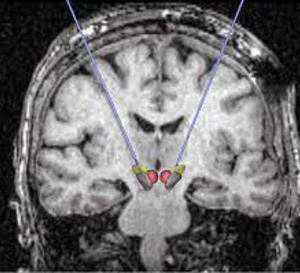

COVID-19 long et atteintes cérébrales : l’imagerie par PET-Scan pourrait lever le doute - 19/04/2022

À retenir Une étude multicentrique s’est intéressée à l’hypométabolisme cérébral détecté par PET-Scan chez des patients ayant été infectés par le SARS-CoV-2 et suspectés de COVID long avec atteinte...